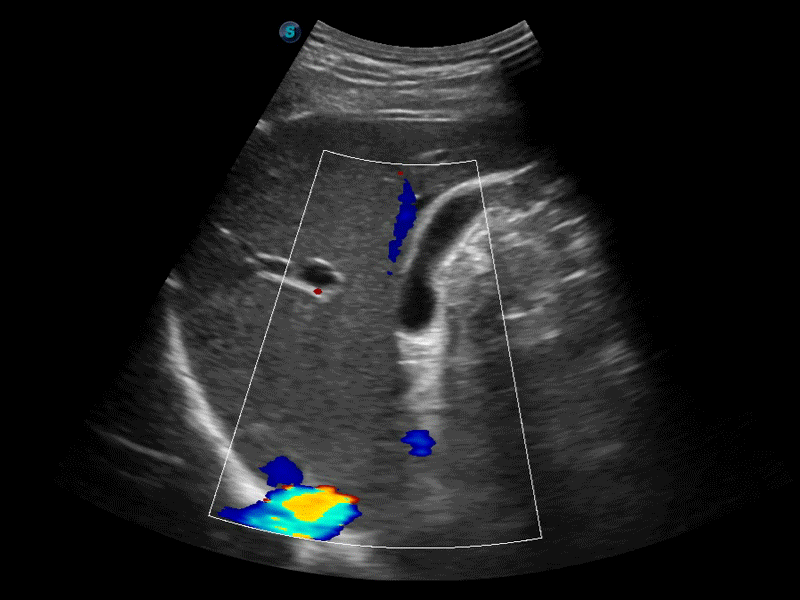

高分辨率血流成像技術提高了對低速血流信號的檢測能力。在提高空間分辨率的同時,也克服了血流外溢現象,為用戶提供更加真實的血流動力學信息。

凸陣、線陣和相控陣探頭進行實時掃描時,開啟擴展成像模式,可以擴展超聲圖像視野,以便更完整地查看大的病灶或組織器官的解剖結構。

通過色彩血流和實時寬景相結合,可觀察到完整的靜脈或動脈的血流,方便醫(yī)生檢查。實時掃查過程中,如有任何操作失誤也可以很容易地進行回掃擦除,而不會中斷掃查。